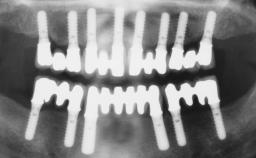

Immediate Loading of Six Implants in the Mandible and Six Implants in the Maxilla and Final Restoration with Full-Arch CAD/CAM Metal Framework FDPs Involving Digital Planning and Guided Surgery

# of Implants 12

Guided Surgery Yes

Abutment Type CAD/CAM

Prosthesis Type FDP